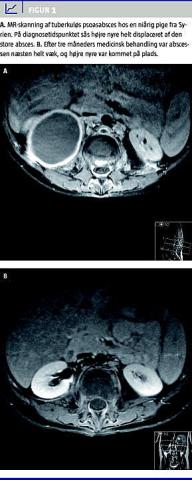

Den hyppigste form for tb i knogler og led er spondylitis tuberculosa (Potts sygdom) efterfulgt af artritis i de vægtbærende led og osteomyelitis uden for columna. Spondylitis tuberculosa sidder oftest i torakalcolumna. Infektionen begynder i den forreste del af corpus vertebra, hvorefter den breder sig til en discus intervertebralis og næste vertebra. Der kan udvikles abscesser paraspinalt eller som psoasabsces (Figur 1 ). Symptomerne begynder med lokaliserede smerter og almene symptomer, men der kan senere komme rodpåvirkning med lammelser til følge. Diagnosen stilles ofte på den kliniske mistanke kombineret med typiske forandringer, der kan ses på en magnetisk resonans (MR)-skanning, da det kan være vanskeligt at få materiale til mikroskopi og dyrkning [12].

Behandlingsvarigheden af tb i knogler og led anbefales forlænget til 9-12 måneder. Hvis der er svære knogledestruktioner eller truende sammenfald af columna, kan det være nødvendigt med operative indgreb, og store abscesser kan kræve drænage.